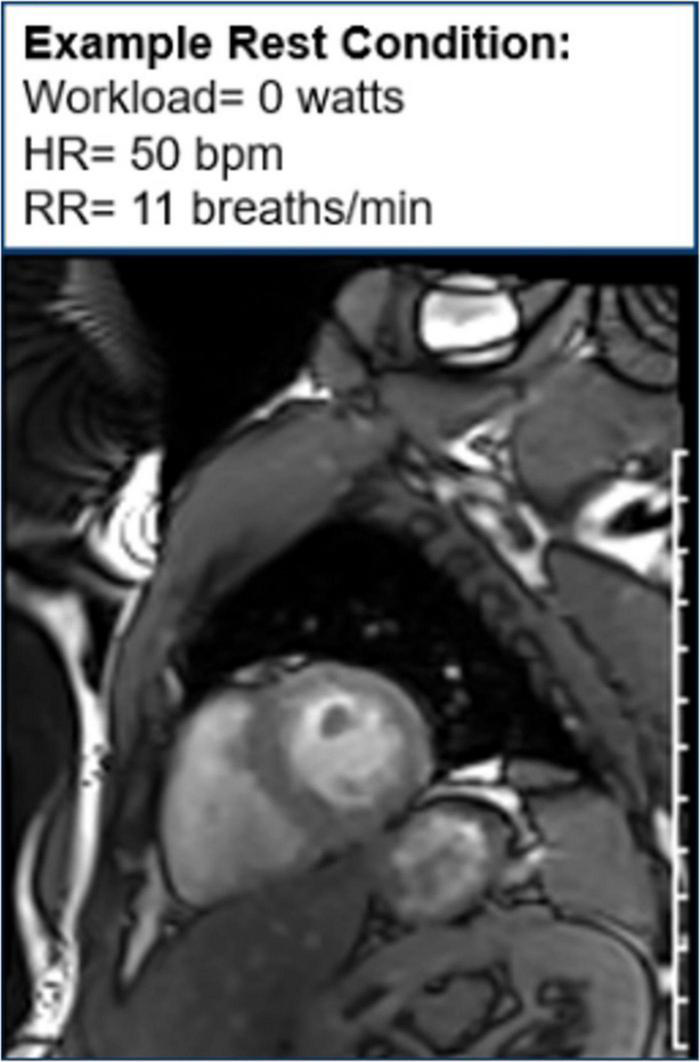

Moreover, CMR can be used to assess cardiac function during exercise testing (72) and has even been utilized in hematologic cancer survivors by placing an exercise bike in the magnetic resonance imaging (MRI) scanner (Figure 10). Cine images at rest and during exercise are depicted (Figures 11, 12), as this technology allows for myocardial function to be compared at baseline and during exercise (73).

FIGURE 10

Study set-up with magnetic resonance imaging (MRI)-compatible exercise bike positioned in CMR imaging scanner. The subject, MRI scanner, MRI-compatible exercise bike, and ventilatory gas analysis are indicated by black arrows. The subject lies outside the MRI scanner and will pedal on an exercise bike as they move through the scanner. Ventilatory gas analysis is simultaneously performed while a cardiac MRI is obtained.

FIGURE 11

Cine image at rest. One image of a cine loop at the end short-axis view of the myocardium. The left ventricle is gray, while the blood pool is white. At rest, the workload is 0 w, and the patient’s heart rate is 50 bpm and respiratory rate is 11 breaths/min.

FIGURE 12

Cine image during exercise. One image of cine loop at the end short-axis view of the myocardium. The left ventricle is gray, while the blood pool is white. During exercise, the workload is 110 w, and the patient’s heart rate is 101 bpm and respiratory rate is 21 breaths/min.